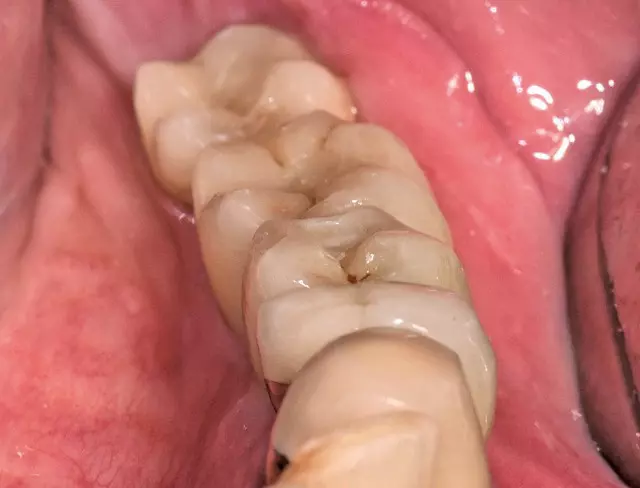

Freilegung und prothetische Versorgung

Die Freilegungsoperation fand nach etwa vier Monaten Einheilzeit statt. Die Implantate zeigten sich regelrecht eingeheilt und gedeckt von einer vitalen Knochenschicht (Abb. 35 und 36). Zur Ausformung der Gingiva wurden die Implantate regio 35 mit einem 4,1 x 3 mm und regio 36 und 37 mit einem 4,5 x 5 mm Gingivaformer versorgt. Zur Gerüsteinprobe (Dentalwerk Nürnberg) drei Wochen nach Eingliederung (Abb. 38) zeigen sich gesunde, reizfreie Schleimhautverhältnisse mit einer ausreichenden Schleimhautdicke (Abb. 37). Abschließend werden die Implantate prothetisch mit einem vollkeramischen Kronenblock (Dentalwerk Nürnberg) drei Wochen nach Freilegung versorgt (Abb. 39a und b). Nach Eingliederung der Prothetik wurde ein abschließendes Kontrollröntgen (Abb. 40) angefertigt, das suffizient eingeheilte Implantate mit mehr als ausreichendem Knochenangebot zeigt.